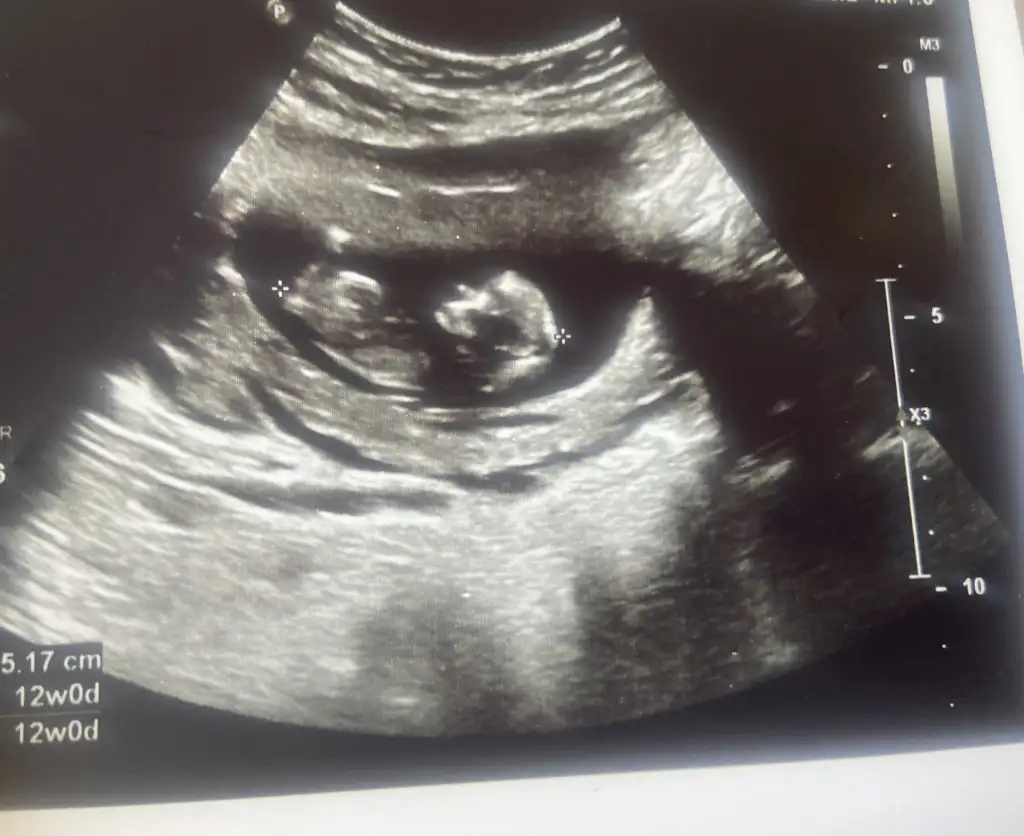

Doktor erkeğe benzetiyorum ama bir sonraki kontrolünde daha net belli olur dedi. İkili testte de ense kalınlığı 1mm çıktı

Merhabalar hanımlar 🌸 12 haftada doktor cinsiyet tahmini yapmadı, sizlerden varsa anlayan yorum yaparsa çok sevinirim 😌

Kızlar selam. Dun kontrolumuz vardı ıkılı testımızı yaptırdık. Once ultrasonda 10-15 dakıka baktı doktorumuz. Baş popo 63 mm. Ense kalınlıgı 1.3 mm geldı. Burun kemıgı olusmus dedı. Mıde , bobrek olusmus dedı. Tek tek baktı. Kalbını dınledık. Zıplıyordu ıcerde 😍🧿 12+1 gelmesı gerekırken 12+4 geldı 🧿 cınsıyet ıcın yapısına gore bır yorum yaptı ama bacak arasını goremedık . Bır ay sonra netlesır dedı. Sızede atayım bı tahmınde bulunur musunuz 😍 ay bıde yan duruyodu dedıkı ıyıkı yuzustu degıl renklı ultrasonda oyle olsa korkarsın bu haftada dedı . Gozler falan yanda daha 🙈♥️🧿